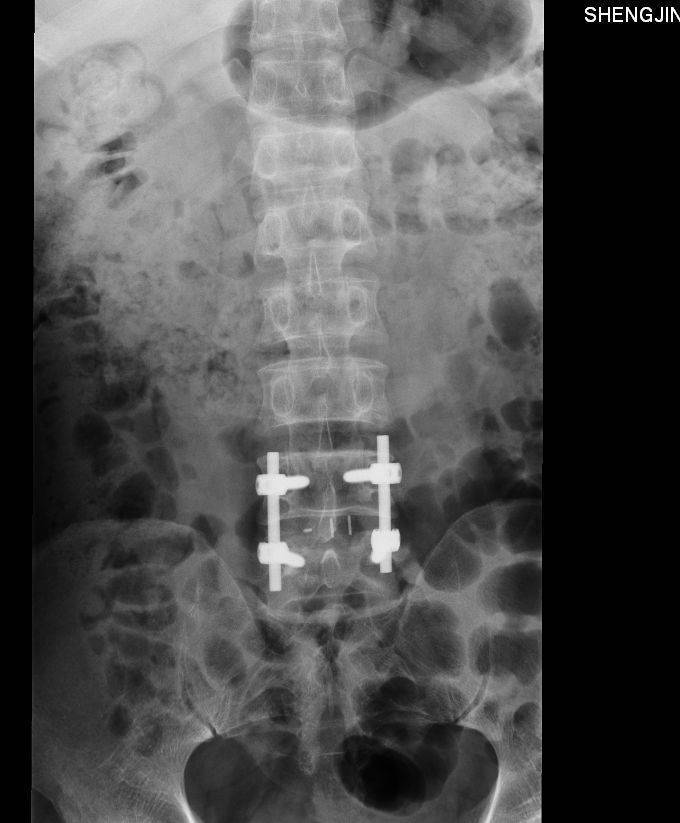

诊断:腰椎间盘脱出症,髓核游离 入院后完善检查,查无手术禁忌症后行腰椎间盘切除椎板减压椎弓根钉椎间融合器植骨内固定术

患者早期手术治疗后,支具保护下可以早期下地,患者腿部疼痛减轻,提高患者生命质量。